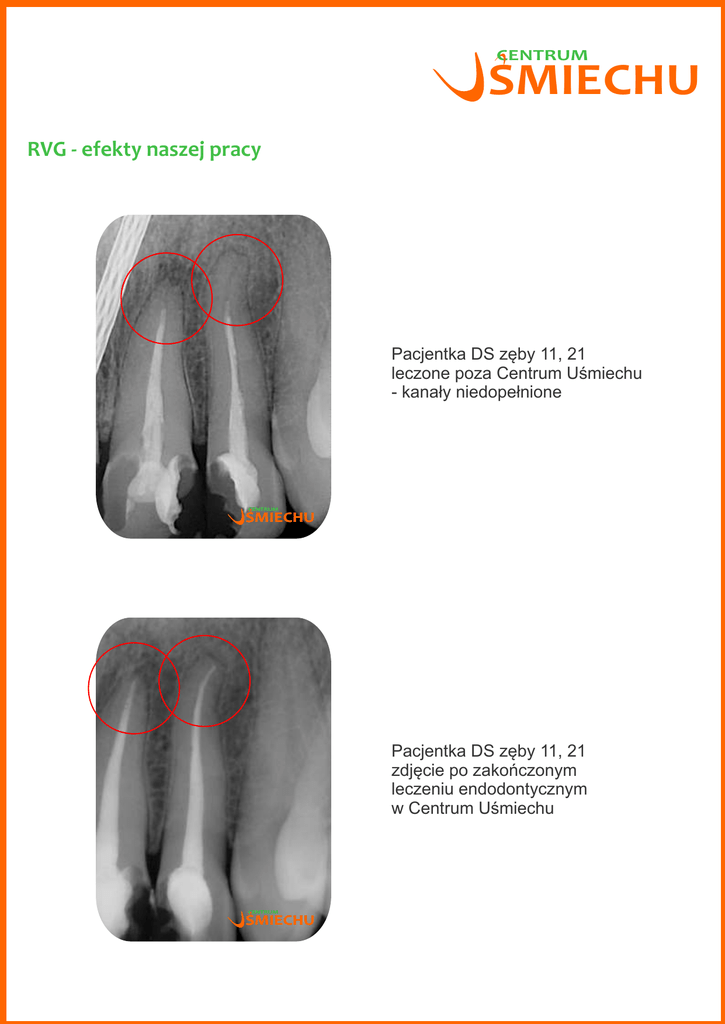

Pacjentka DS zęby 11, 21

zdjęcie po zakończonym

leczeniu endodontycznym

w Centrum Uśmiechu